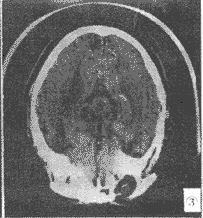

腦CT酒精中毒性神經疾病的中樞神經抑制症狀,應注意與引起昏迷的疾病相鑑別,如鎮靜催眠藥中毒、一氧化碳中毒腦卒中、顱腦外傷等戒斷綜合徵的精神症狀和癲癇發作,應與精神病、癲癇、窒息性氣體中毒低血糖征等相鑑別慢性酒精中毒的智慧型障礙和人格改變,應與其他原因引起的痴呆鑑別。

其它輔助檢查:1.心電圖、腦電圖、腦CT或MRI檢查,有鑑別診斷及中毒程度評估意義;2.肌電圖和神經電生理檢查有鑑別診斷意義。